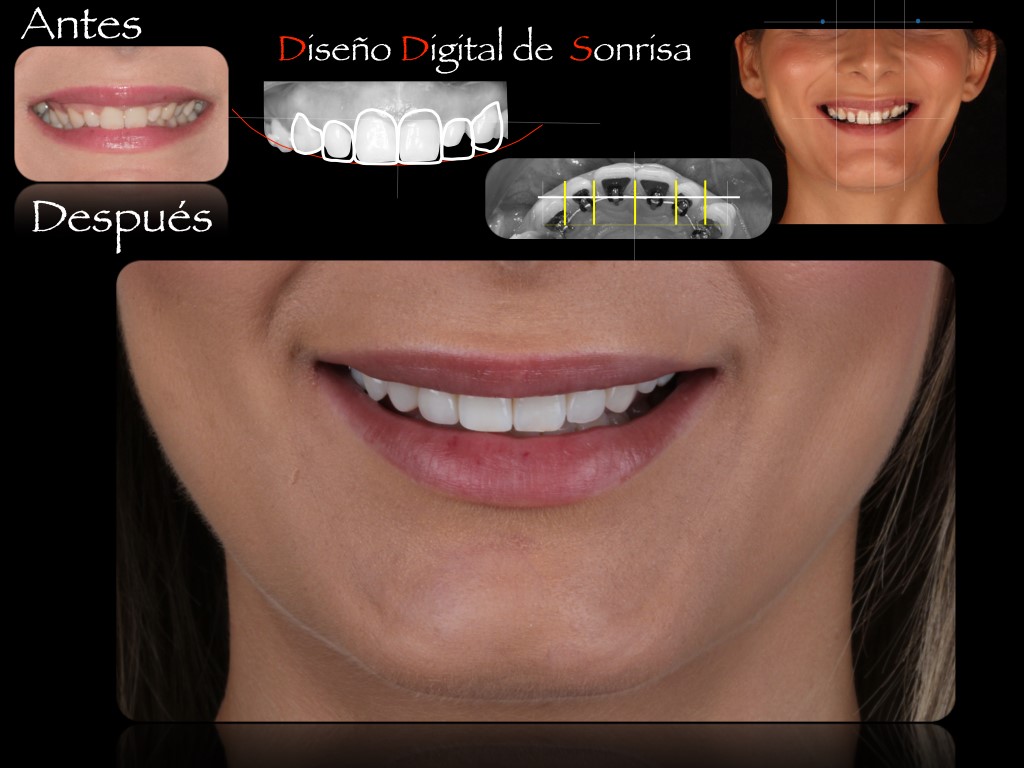

Descúbrelo en Ortoperio, tu clínica dental en Murcia, a través del Diseño Digital de la Sonrisa: